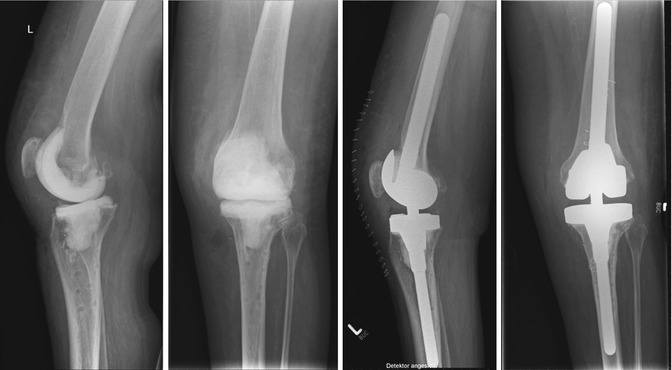

In total knee replacement (also known as total knee arthroplasty, or TKA), the joint’s bone-end surfaces are resurfaced with man-made materials. In total knee arthroplasty, the implant (prosthesis) design may vary according to your needs, but the most common implant consists of three component parts. The patella, or knee cap, is made of high-density polyethylene, which offers tremendous strength and durability. The femoral section, or thigh bone, is metal, while the tibia, or shin bone, is made of metal tray with high density polyethylene cushioning attached to the tray. The implants are held in place with Bone Cement.

In Partial Knee Replacement, also known as Unicompartmental knee replacement, only the affected compartment usually medial compartment is replaced. The criteria for patient selection for this limited version of knee replacement are strict and the chosen patient has a faster rehabilitation with good results